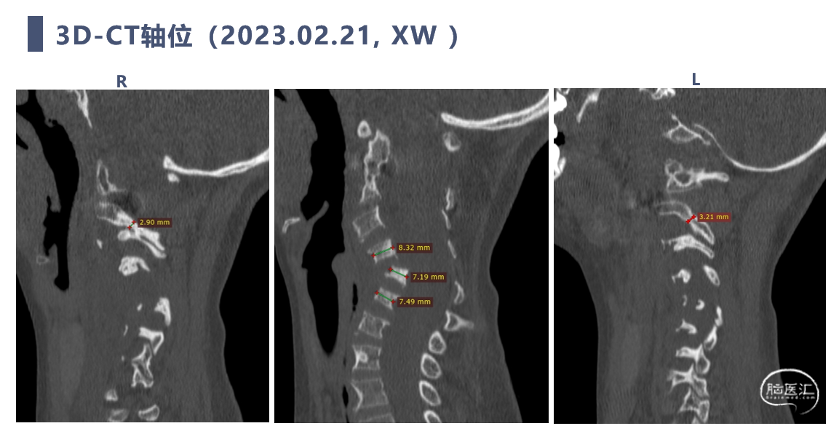

CT

CT显示颈椎椎体最大深度只有8mm,枢椎椎弓根直径3.2mm